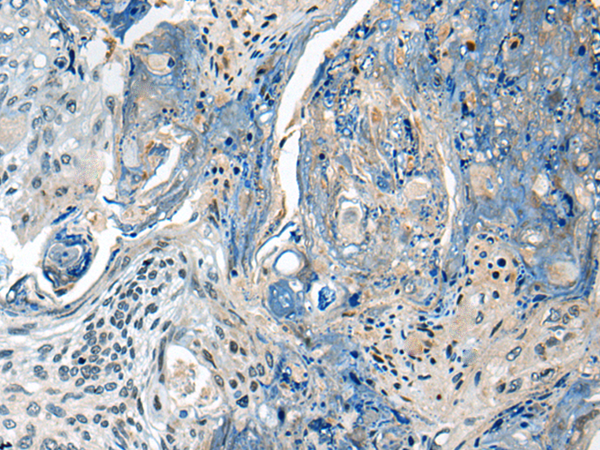

分类: 科研抗体货号: P02532别名: ENTH; EPN4; EPNR; CLINT应用: WB,IHC反应种属: Human, Mouse